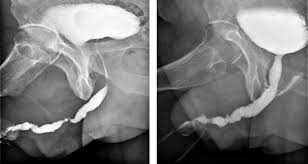

Hipospadias Uretra

Hipospadias Uretra from www.uretra.es

Hipospadias Ameliyatlarindaki Tedavi Yaklasimlari Prof Dr Y Tarkan Soygur

Hipospadias Ameliyatlarindaki Tedavi Yaklasimlari Prof Dr Y Tarkan Soygur from www.tarkansoygur.com

Andrologia Hipospadia

Andrologia Hipospadia from 2.bp.blogspot.com